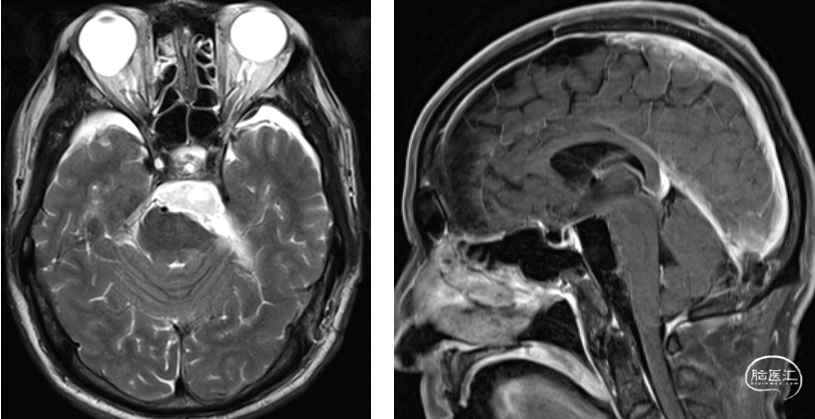

术前检查

![]()